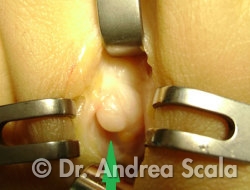

Una minuta incisione consente di accertare la presenza del “neuroma di Morton”.

La foto dell’intervento mostra che in questo caso il nervo ingrossato (neuroma) è stato liberato dalle aderenze e dalla infiammazione dei tessuti circostanti che lo comprimevano (intervento di neurolisi).

Dopo aver eliminato la compressione, si vedono i due rami nervosi digitali che si dirigono senza ostacoli e senza vincoli verso le dita del piede.